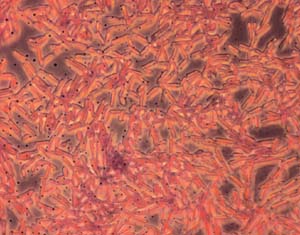

C. parapsilosis growing as a biofilm on a plastic surface

When the yeast is growing on the plastic surfaces of these devices it forms a structure called a 'biofilm'. Biofilms form when the yeast adhere to surfaces, rather than living freely in culture. They are very resistant to treatment with antifungal drugs, and often the infected device has to be removed.